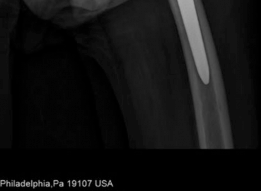

For anyone wondering about Acetabular Revision: Solving Challenges Post Two-Stage Arthroplasty, A **title acetabular revision** is a complex procedure addressing issues like septic loosening, dislocation, and significant osteolysis in total hip arthroplasty. For a 71-year-old male with a dislocated left THA due to infection and periacetabular bone loss, treatment involved a two-stage exchange followed by revision with a press-fit hemispherical cup and screw fixation.

In cases of a well-fixed femoral stem that impedes acetabular exposure, or when simultaneous femoral revision is required, an Extended Trochanteric Osteotomy is highly recommended. The Extended Trochanteric Osteotomy provides unparalleled, extensile exposure to the acetabulum, facilitates safe extraction of the femoral component, and protects the abductor mechanism.